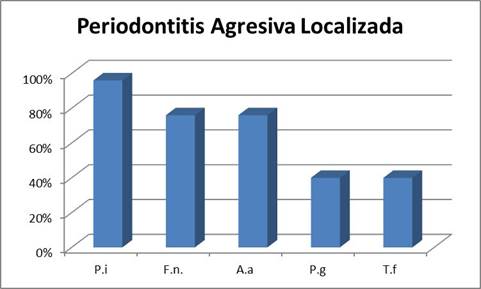

Periodontitis Agresiva Localizada

En cuanto al cuadro localizado el microorganismo más prevalente fue P. intermedia presentándose en el 96% de los pacientes, seguido de F. nucleatum y A. actinomycetemcomitans ambos con una prevalencia en el entorno del 75%. Se destaca la mayor prevalencia de A. actinomycetemcomitans que en los cuadros generalizados. Esto es concordante con la importancia que tiene este microorganismo en los cuadros localizados 13-15. Finalmente, los microorganismos P. gingivalis y T. forsyhtia presentaron la menor prevalencia detectándose en el 40% de los pacientes estudiados (Gráf. 3).